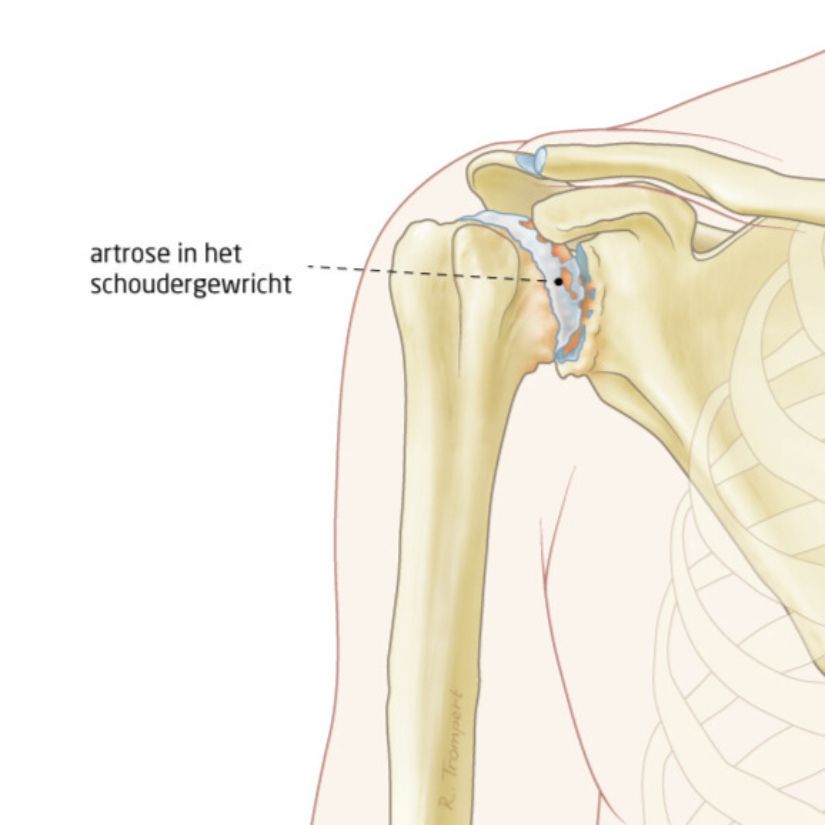

Hoe komen we erachter wat de klachten veroorzaakt?

Dit doen we vooral door te luisteren naar de klachten. Daarna onderzoeken we de schouder.

Een röntgenfoto geeft zekerheid over de diagnose. Daarop kunnen we zien dat de ruimte tussen de kop en kom smaller is dan normaal. Dat is een teken dat het kraakbeen op de botten is weggesleten. Verder kunnen we zien of er extra bot is aangegroeid (osteofyten).

We kunnen de mate van slijtage een ‘score’ geven op de röntgenfoto. Van klasse 1 (bijna geen slijtage) tot klasse 4 (vrijwel volledige slijtage van het kraakbeen).

Oorzaken

De slijtage kan verschillende oorzaken hebben. Deze zijn:

• langdurige, zware belasting van de arm. Bijvoorbeeld tijdens werk of tijdens bepaalde sporten.

• een lang bestaande grote scheur in een of meer pezen van de schouder (rotator cuff ruptuur). De kop staat daardoor niet meer perfect in de kom. Daardoor slijt het kraakbeen sneller. Dit heet dan ‘rotator cuff artropathie’.

• een schouder die vaak uit de kom gaat. Echte slijtage ontstaat pas als de schouder gedurende een lange periode vaker uit de kom gaat.

• reuma of een andere gewrichtsontsteking.

• vervorming van de schouderkop of schouderkom na een botbreuk in het verleden. Door de vervorming slijt het kraakbeen sneller.

• een infectie van het schoudergewricht.

• afsterven van de botcellen van de schouderkop door te weinig bloedaanvoer. Dit noemen we avasculaire necrose. Dit kan komen door langdurig gebruik van alcohol of van sommige medicijnen (o.a. corticosteroïden).